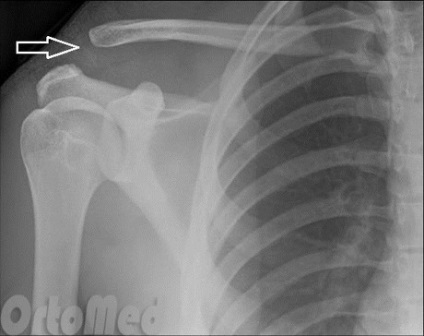

Cu raze X a articulației umărului este realizată pentru diagnostic podstverzhdeniya. Pe radiografia arată în mod clar, dacă a existat o dislocare a capătului acromiala al claviculei.